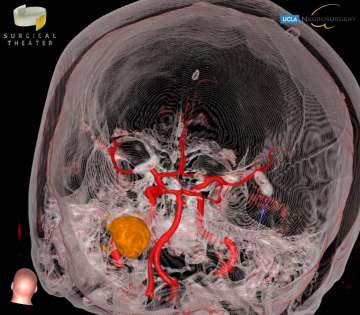

Medical scan shows a brain's blood vessels in blue and red, with a beige tumor highlighted in the center. Click image to enlarge

Medulloblastomas are the most common malignant brain tumors found in children. Between 250 and 500 children under the age of 16 are diagnosed with medulloblastoma each year in the United States, and it accounts for nearly 20% of all childhood brain tumors. Presenting symptoms are usually from obstructive hydrocephalus, and typically include headaches, nausea and vomitting, clumsiness, visual changes, and issues with coordination. Surgery is the first step in treating medulloblastoma, followed by chemotherapy and/or radiation therapy. The survival rates in children depend on the surgeon’s ability to safely and completely remove the tumor, and the sub-type of medulloblastoma. With optimal care, long-term survival rates can be better than 80%.